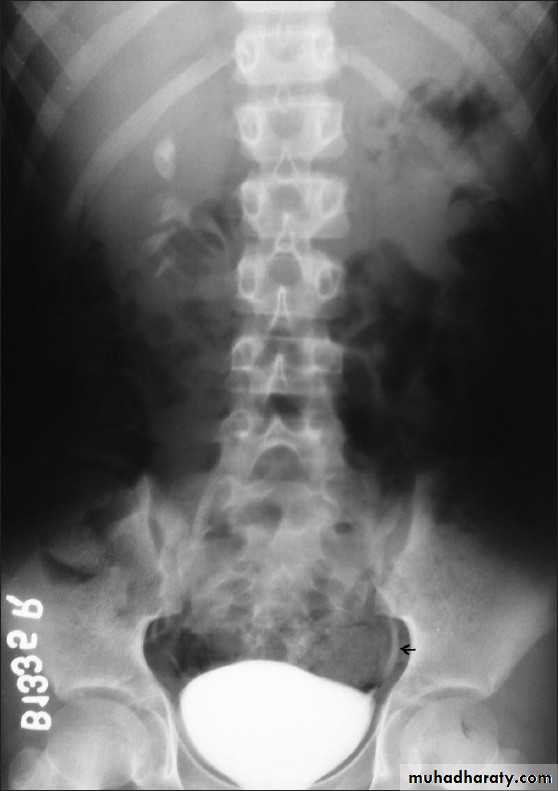

22- PUJ obstruction23- horse shoe24- PUJ obstruction25- double ureter26- partial PUJ obstruction27- double ureter28- schistosoma of bladder29- filling defect in the pelvi-calycial system30- tumor 31- filling defect (stone)